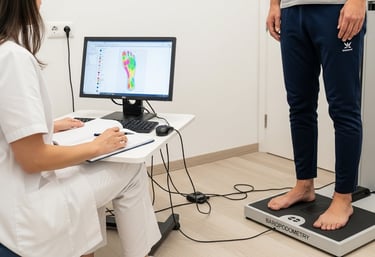

Baropodometria computadorizada